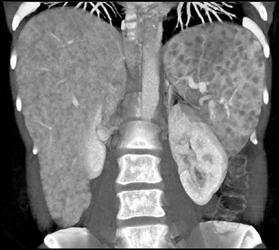

Sarcoidosis